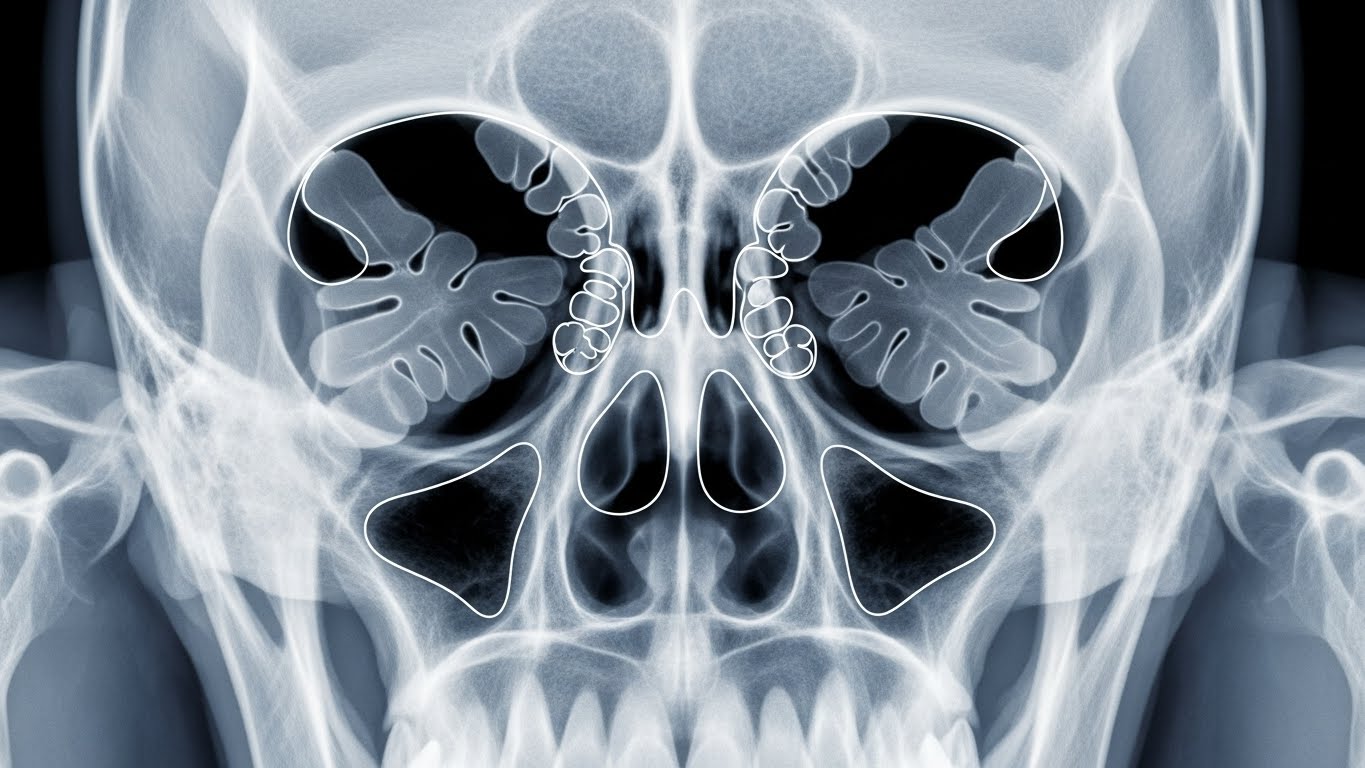

부비동염을 이해하려면 먼저 우리 얼굴 뼈 속에 있는 '부비동(Paranasal Sinus)'이라는 공간을 알아야 합니다.

우리 코 주위의 얼굴 뼈 속에는 비어있는 공간들이 있습니다. 이것을 '부비동'이라고 하는데요. 이 공간은 좁은 통로(자연공)를 통해 콧속과 연결되어 있습니다. 평소에는 이 공간에 공기가 차 있고, 부비동 내에서 만들어진 분비물은 자연공을 통해 콧속으로 배출됩니다.